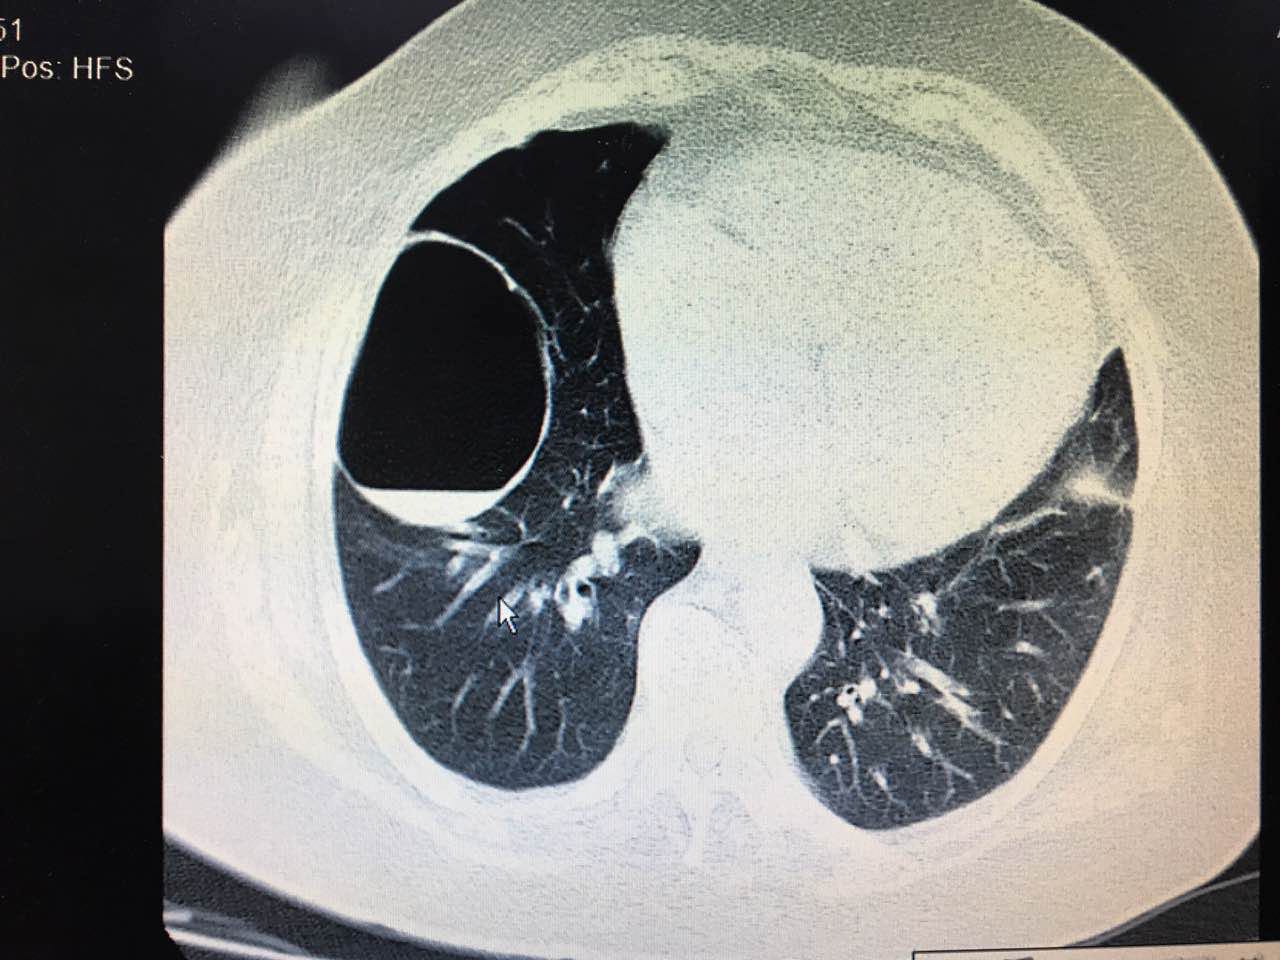

1. 个体化评估:通过CT等影像检查明确囊肿特征,由呼吸科或胸外科医生评估风险等级。

肺囊肿是一种肺部异常空腔结构,可能先天形成或后天获得。对于足球运动这种高强度有氧活动,肺囊肿的影响因人而异,主要取决于囊肿的大小、位置和是否引发并发症。